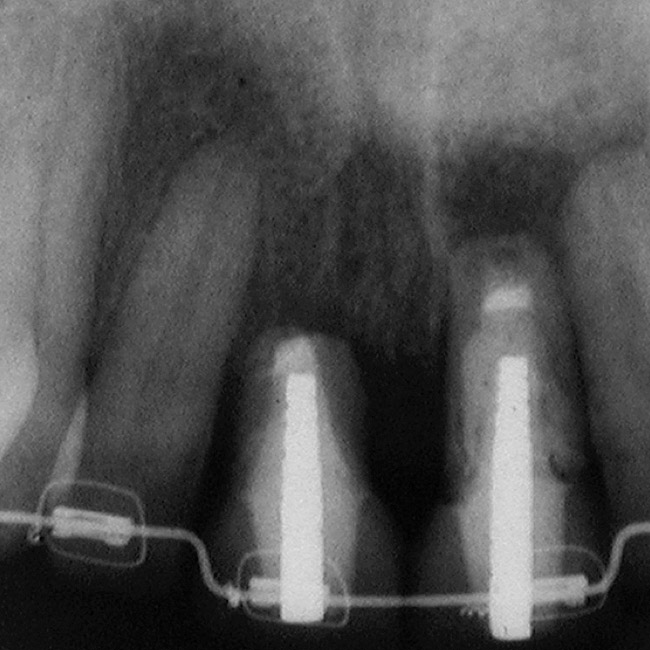

Figure 6  Excellent interproximal crestal bone level between the centrals before extraction.

Figure 6

Figure 8  Maintenance of interproximal crestal bone following final restoration placement.

Figure 8